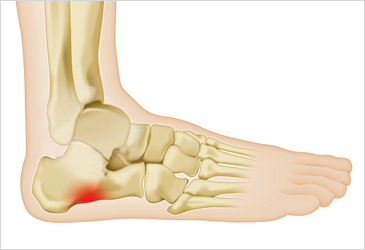

8. 발바닥에 딱딱한 결절

일부 환자들은 발꿈치에 결절이 생길 수 있습니다. 결절은 발꿈치 뼈에 작은 돌출부위로, 족저 근막염이 장기화되면 나타날 수 있습니다. 이 결절은 발꿈치를 눌렀을 때 통증을 유발합니다.